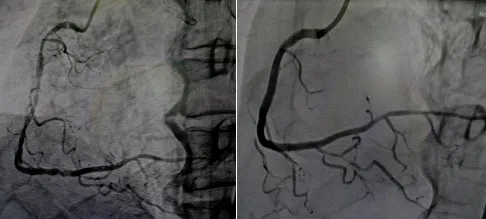

56岁的李女士因急性冠脉综合征入院。造影检查发现,其右冠存在弥漫性重度狭窄,病变部位为深层环形钙化——这种钙化藏匿于血管壁深处,处理不当极易导致支架膨胀不全,远期血栓风险高。

面对这一特殊病变,心血管内一科介入团队果断采用国际前沿的振波球囊技术。术中,医生将振波球囊精准送达钙化病变处。随着球囊低压扩张,超声冲击波由内向外穿透血管壁,精准震碎深层的钙化环,而血管软组织毫发无损。

冲击波发射完毕后,原本“硬如磐石”的血管恢复了良好的顺应性。医生顺利植入支架,支架很好贴合血管壁。术后,李女士恢复良好,次日即可下床活动。